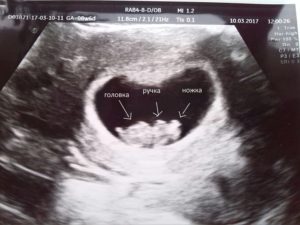

Аппарат УЗИ (ультразвукового исследования) позволит установить наличие/отсутствие сердцебиения, понять нормально ли развивается плод, соответствует ли его размер сроку беременности.

Стоит отметить, что благодаря УЗИ можно увидеть голову ребенка, его движения, желточный мешок. Обязательным является фиксация веса будущей мамы, пока еще он не прибавляется, но именно с этого дня начинается пристальное наблюдение за этим показателем.

На 8 неделе размер плода можно сравнить с черешней. На УЗИ специалист увидит движение конечностями, которые он совершает. Плод увеличивается каждые сутки на 1 мм.

Установить вероятность ЗБ на 7-8 неделе можно при помощи анализа на ХГЧ (Хорионический гонадотропин человека). Когда беременность протекает нормально, этот показатель увеличивается в разы каждые два дня, соответственно, если беременность не развивается, то и показатель останется прежним.